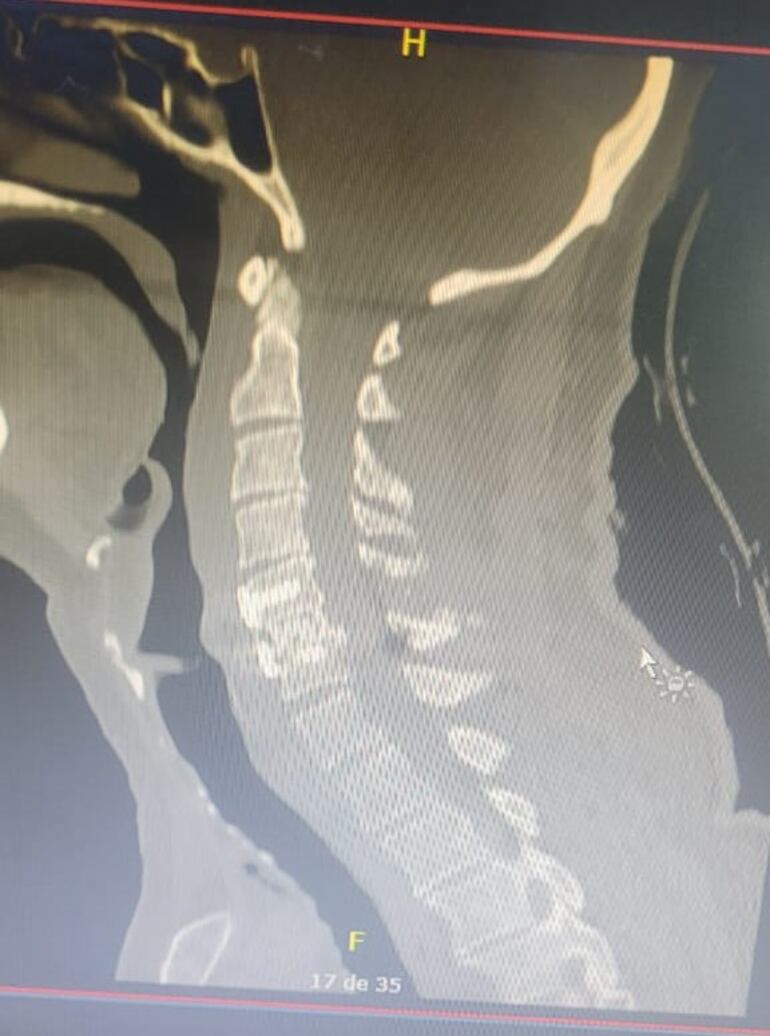

Un paciente de 70 años, víctima de un accidente de tránsito, fue sometido a una artrodesis cervical de doble vía tras presentar una luxación C5-C6 con compresión medular. Con la misma, se logró impedir que el paciente quede en silla de ruedas.

El equipo quirúrgico liderado por Néstor Romero, neurocirujano, junto a Juan José Jara, neurocirujano, y el anestesiólogo, Roberto Bruzzone, lograron una intervención exitosa. El paciente fue dado de alta en 72 horas, sin déficit motor y caminando, con una sola cirugía.